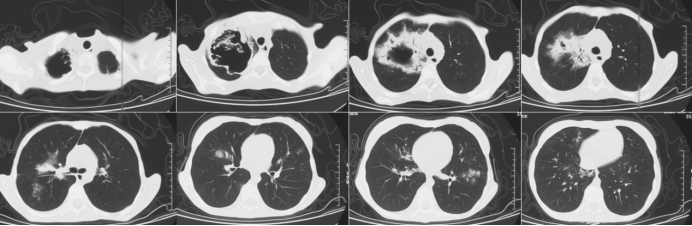

实施优化引流方案10~15天后,患者脓腔冲洗液逐渐清澈、痰量减少;2024年2月19日复查胸部CT显示右肺上叶空洞缩小、气液平面消失,最终顺利转出MICU(2024年3月8日),肺部病变持续吸收。患者治疗过程中胸部CT变化情况如图3所示。

图3 患者胸部CT变化情况